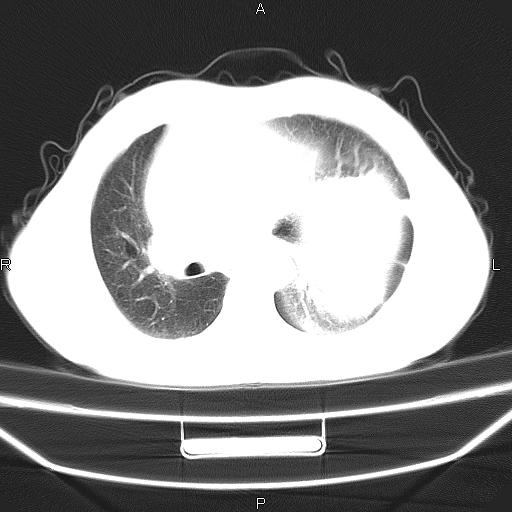

患者,男。50岁。近几日有咳嗽症状,无其他不适,既往病史无,考虑膈疝。请前辈们看看指导指导。

膈膨升,左下肺通气不良,膈肌好像还完整。

考虑左侧膈疝。

左侧膈疝。

符合隔膨升,膈肌较完整。